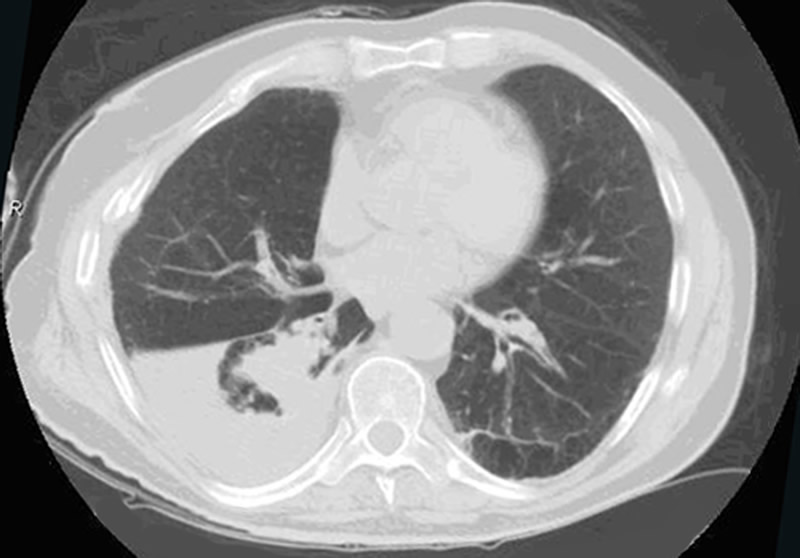

Although surgical management of patients with severe flail chest is at present controversial, we think that surgical stabilization is strongly indicated in specific clinical situations. The effectiveness and the ideal timing of chest wall stabilization in patients on mechanical ventilation is related to the degree of the pulmonary parenchymal damage [7,8]. The presence of extensive pulmonary contusion (Figure 1) is a relative contraindication to surgical stabilization. These patients require prolonged ventilation, and an early surgical stabilization would not provide benefit [7,8]. However, a surgical procedure can be proposed if the patient fails to wean from the ventilator once a partial resolution of pulmonary contusion is achieved [9,10].

Figure 1. Blunt chest trauma with left flail chest and ipsilateral severe pulmonary contusion and posttraumtic pneumothorax on the right. Figure 2. Blunt chest trauma with right flail chest with ipsilateral pleural effusion and mild pulmonary atelectasis

In patients with isolated blunt chest trauma who have severe flail chest without significant pulmonary contusion, prolonged internal pneumatic stabilization is not suitable because of the risk of ventilator-related infectious complications. Moreover, mechanical ventilation is not always successful in preventing chest wall deformities that may result in a subsequent respiratory restrictive dysfunction [10,11]. In patients with mild or no pulmonary contusions (Figure 2), early surgical stabilization (within few days of internal pneumatic stabilization) may result in shorter intensive care unit stay with lower morbidity and prevention of pulmonary restrictive complications resulting in working incapacity [9].